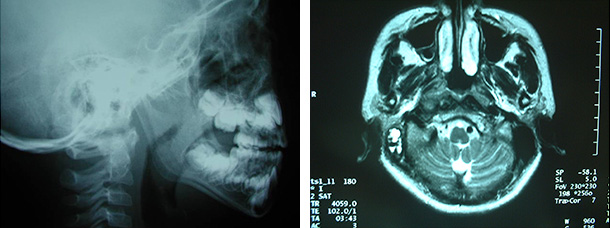

アデノイド増殖症耳鼻咽喉科の病気耳鼻咽喉科専門 医療法人財団 神尾記念病院。

アデノイド増殖症あでのいどぞうしょくしょう とは済生会。